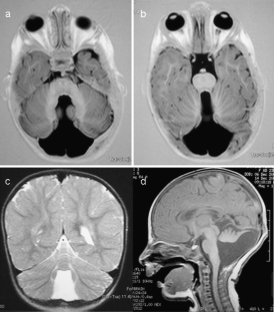

Fibroblast growth factors (FGFs) are important signaling molecules which act during early vertebrate central nervous system development. FGF17, together with FGF8, is a key factor in the patterning of the mid-hindbrain region with a complex picture of spatiotemporal gene expression during the various stages of cerebellar development. Disruption or reduced expression of fgf17 in mice has been associated with cerebellar vermis abnormalities. We have identified a de novo 2.3-Mb deletion of chromosome 8p21.2-p21.3 in a girl with severe growth retardation, seizures, and classical Dandy–Walker malformation. Analysis of gene expression in blood lymphocytes and skin fibroblasts revealed markedly reduced levels of FGF17, which is located 1 Mb from the proximal deletion breakpoint. This is the first report of a human cerebellar malformation associated with transcriptional downregulation of the FGF17 gene.